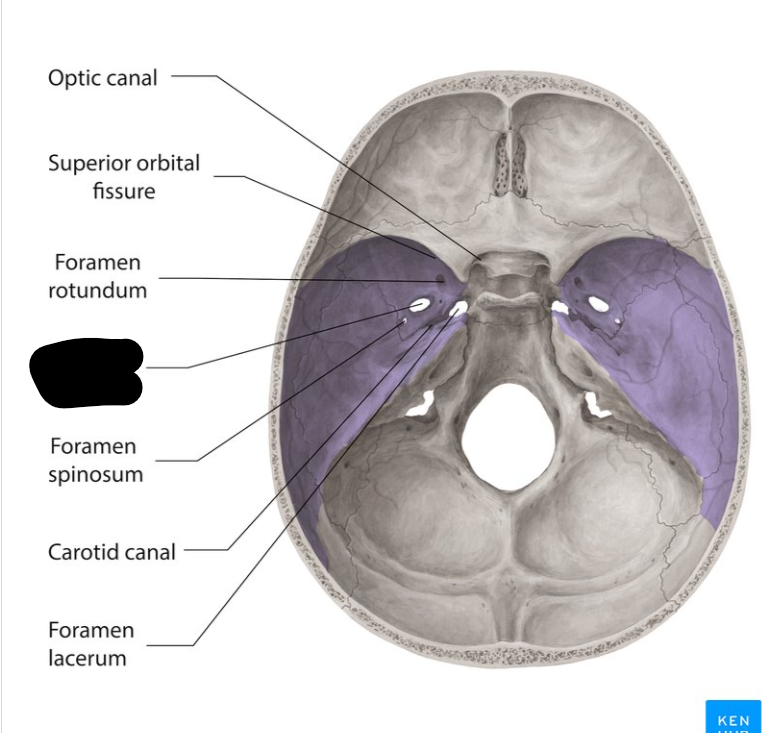

Middle cranial fossa

Foramen rotandum

Foramen ovale

Foramen lacerum

Foramen spinosum

Superior orbital fissure

Optic canal

Carotid canal